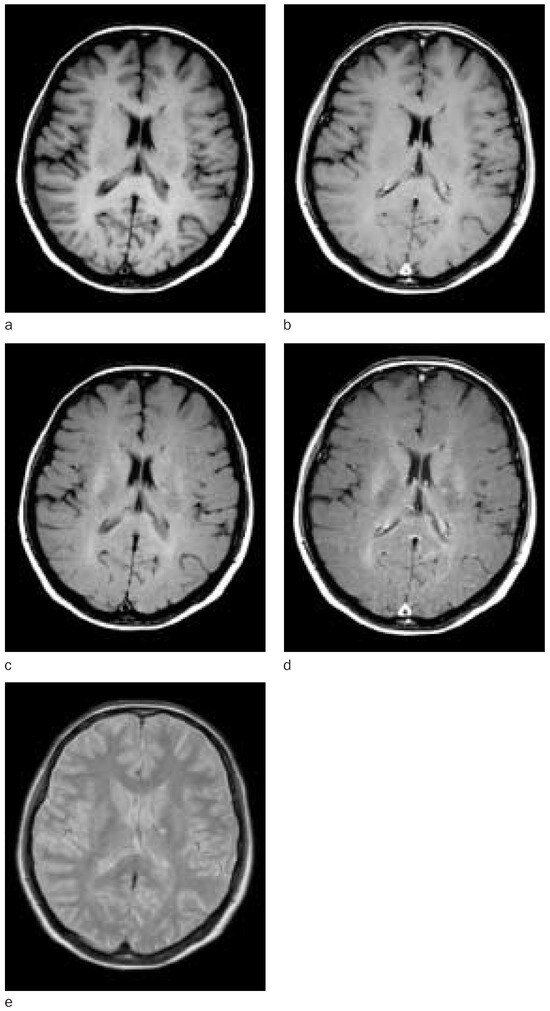

Stellenwert der Magnetresonanztomographie bei Diagnose und Krankheitsmonitoring der Multiplen Sklerose

by P. Freitag, L. Kappos and E. W. Radü

Magnetic resonance imaging (MRI) is currently the best method for imaging multiple sclerosis. Although there is only a weak correlation between clinical disease evolution and conventional magnetic resonance imaging findings, it is a very sensitive method which provides important additional information both in individual case studies and in therapeutic trials. In this review the impact of MRI in diagnosis, prognosis, follow-up and treatment control in multiple sclerosis patients is shown with respect to the different disease courses. More re-cent MR techniques like magnetisation transfer imaging, proton magnetic resonance spectroscopy, measurements of atrophy, functional magnetic resonance imaging (fMRI) and diffusion weighted magnetic resonance imaging are explained. Their contribution for the understanding of pathophysiological and pathoanatomical disease processes in multiple sclerosis and the improvement of clinical correlation between MRI and disease course is discussed. Full article

Show Figures

Figure 1